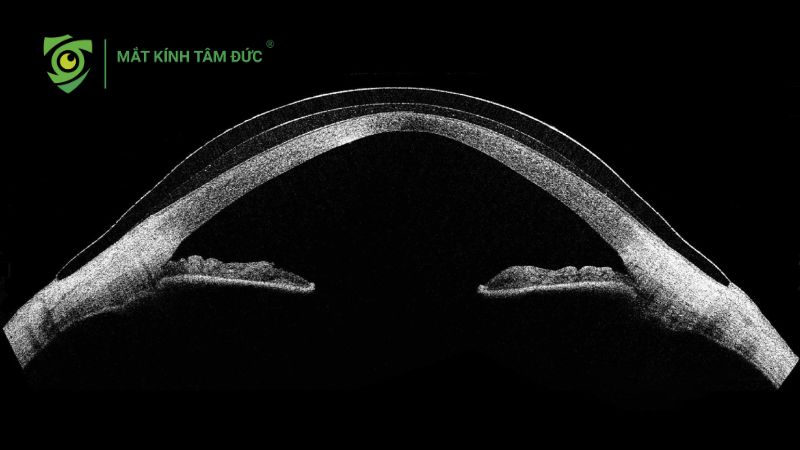

Giác mạc hình chóp là tình trạng giác mạc bị mỏng dần và phồng ra phía trước tạo thành hình chóp thay vì độ cong tròn tự nhiên. Sự biến dạng này khiến ánh sáng khi đi vào mắt không còn hội tụ chính xác, từ đó gây ra tật khúc xạ không đều và làm người bệnh nhìn mờ, méo hình.

Bệnh thường tiến triển âm thầm trong nhiều năm. Giai đoạn đầu, người bệnh chỉ cảm thấy tăng độ cận hoặc loạn thị nhanh. Khi giác mạc càng lồi, thị lực giảm và kính thông thường không còn mang lại hiệu quả rõ rệt. Nếu không được theo dõi và can thiệp kịp thời, giác mạc hình chóp có thể dẫn đến sẹo giác mạc, thậm chí phải ghép giác mạc ở giai đoạn nặng.